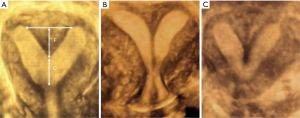

Ultrasound findings of the complete septate uterus and incomplete septate uterus were as follows: the coronal plane of the uterus showed a flat, slightly bulging or slightly depressed (<1 cm) uterus. The uterine cavity of the incomplete septate uterus was “Y” shaped; the complete septate uterus with a double cervical cervix showed the “8” shape; the “V” shape was shown by the complete septate uterus, the separation tube reached the intrauterine mouth, and the single cervical canal (Figure 1).